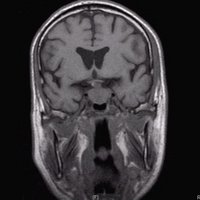

Hypophysenadenom

Hypophysenadenom T1 cor